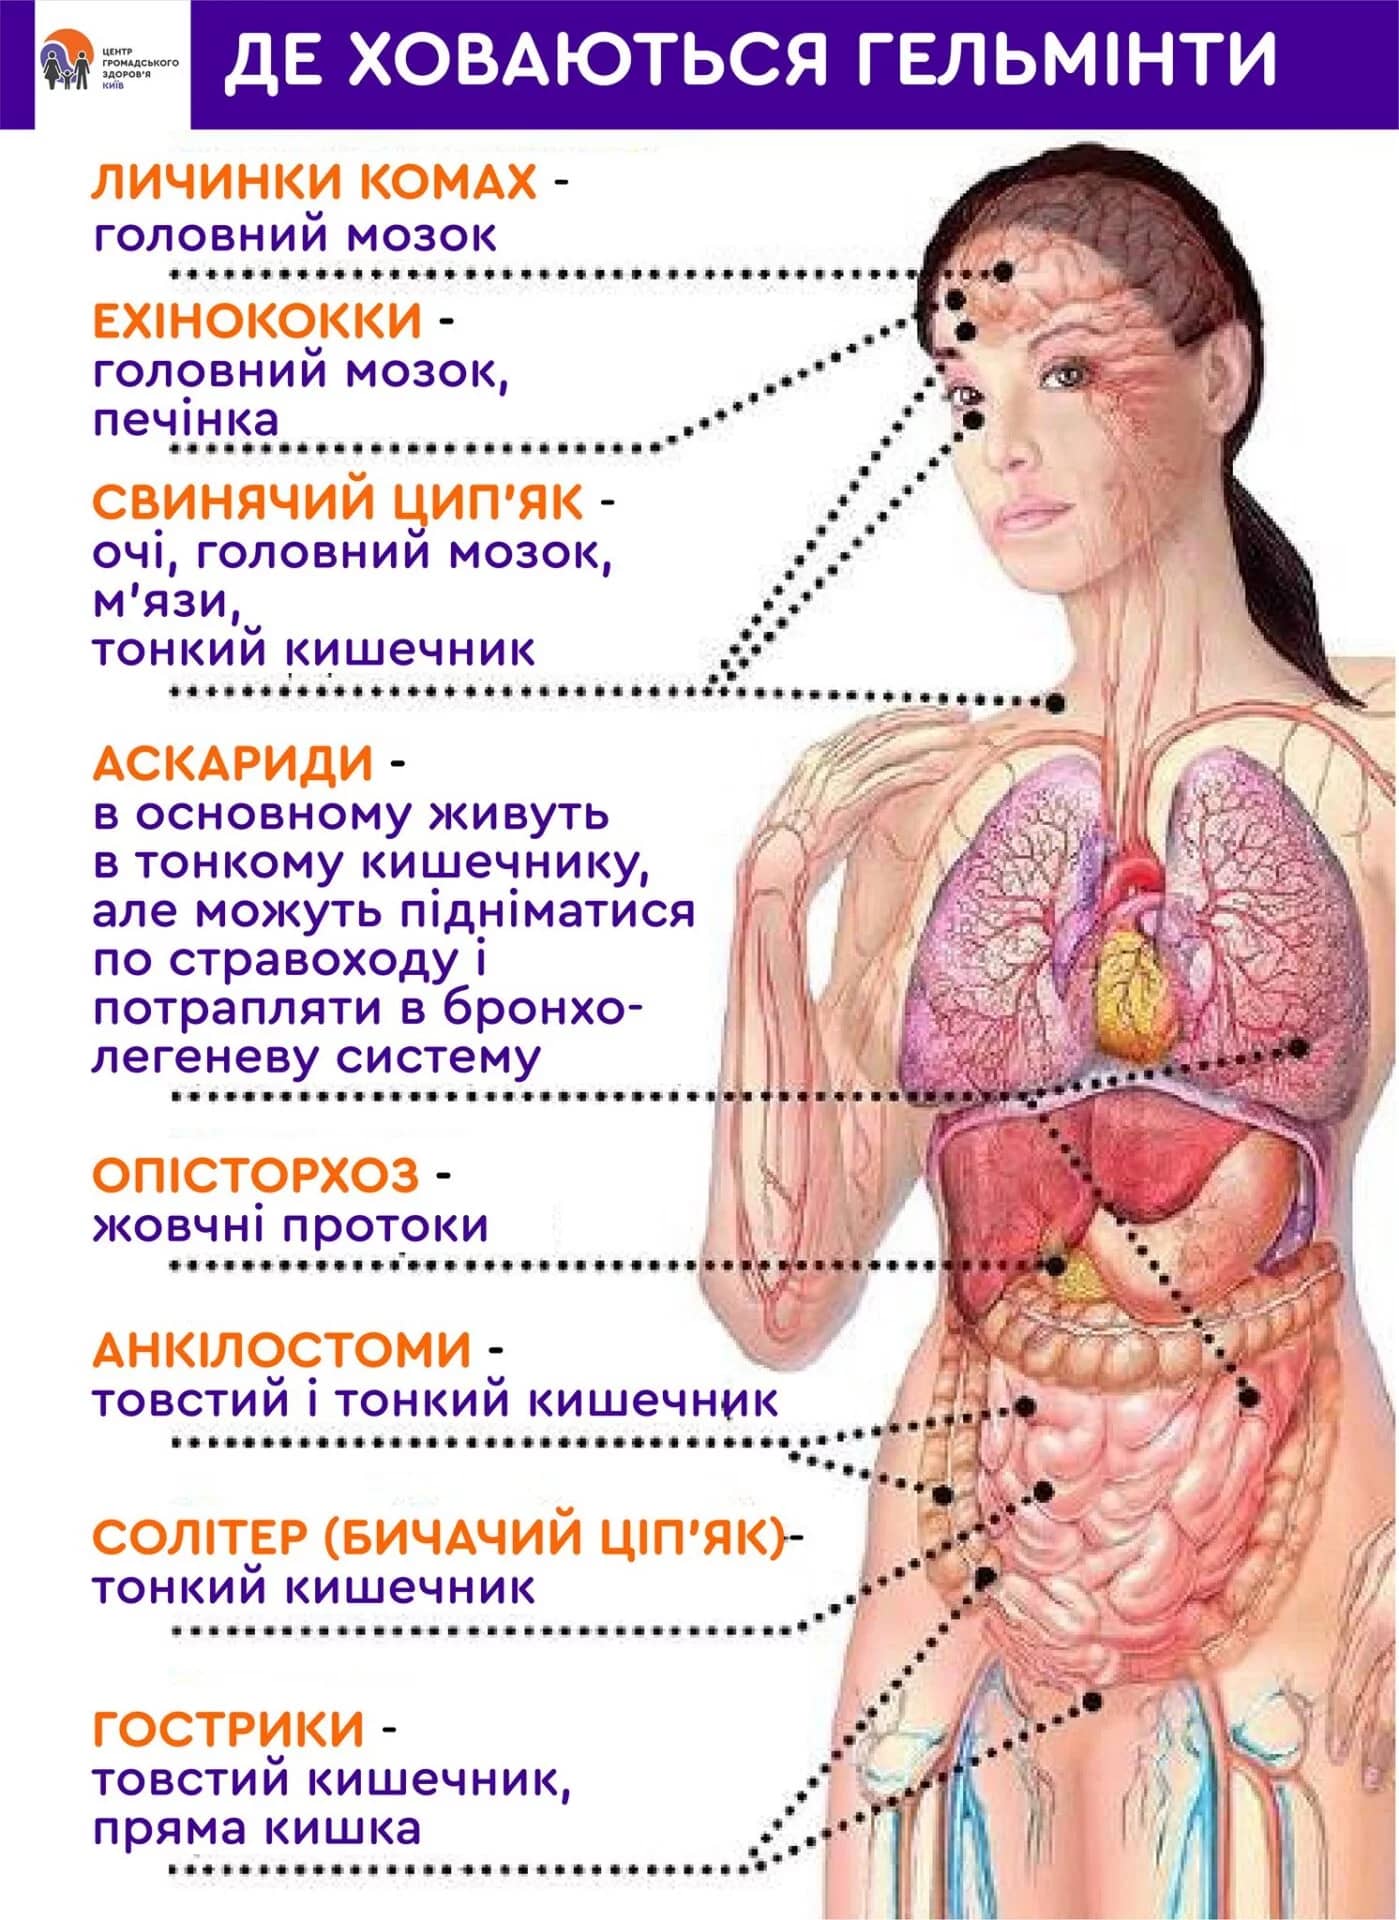

О.Ю. Гришин: Так воно і є насправді. Практично в 90% випадків, коли я роблю розтин, бачу страшну картину. Тіла померлих кишать паразитами! І я спостерігаю їх не тільки в шлунково-кишковому тракті, як багато хто думає. Паразити часто живуть у легенях, серці, печінці й навіть у мозку! Їхні колонії населяють внутрішні органи, а личинки харчуються тканинами живих людей!

Я працюю патологоанатомом багато років. Я бачив таке, що волосся стає дибки! Люди недооцінюють небезпеки, вони думають, що паразити - це глисти, які живуть у кишках. Але це не зовсім так. Існує величезна кількість видів паразитів. Наприклад, є мікроскопічні, але дуже токсичні. Вони отруюють ваш організм, проникають у кров, у серце, виснажують його своїми токсинами, призводять до ішемії, серцевої недостатності, гіпертонії, і, як наслідок, - інфарктів та інсультів. Вони оселяються в легенях, печінці, проникають у мозок і навіть живуть в очах!

Представниками гельмінтів, що вражають життєво важливі органи, є Taenia solium, ехінокок (Echinococcus granulosus), трихінела (Trichinella spiralis). Ехінокок являє собою личинкову стадію гельмінта з роду Echinococcus. І це далеко не всі види паразитів, здатні убити людину.